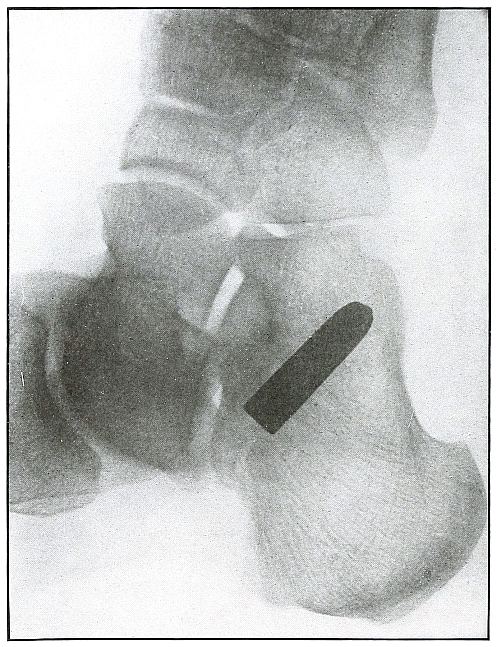

Rifle—Plate 7.

SPINAL REGION.

Gunshot Wound of the Spinal Region,

with Lodgment of the Missile.

The bullet was either dum-dummed or unjacketed because its soft nose

mushroomed, striking the crest of the ilium, penetrated the lumbar

muscles, and struck the side body of the third lumbar vertebra without

producing fracture.

The exposure, as the spinous processes show, was made with the spine

next to the plate, and the slight shadow, somewhat larger than the

projectile—to judge the size from the undeformed diameter—shows

it to be anterior to the vertebra. The shadow is deep enough to indicate

the location fairly near to the plate, and, almost certainly, not in

the abdominal cavity, where the distance from the plate would have

made the shadow less dense and the movement of respiration probably

would have given it a blurred outline. The shadow of the localizing

cross gives a standard of density to be compared with the shadow of

the projectile in making the estimation.

The treatment is conservative; only pain, paralysis, impaired

function, or sepsis indicate interference.